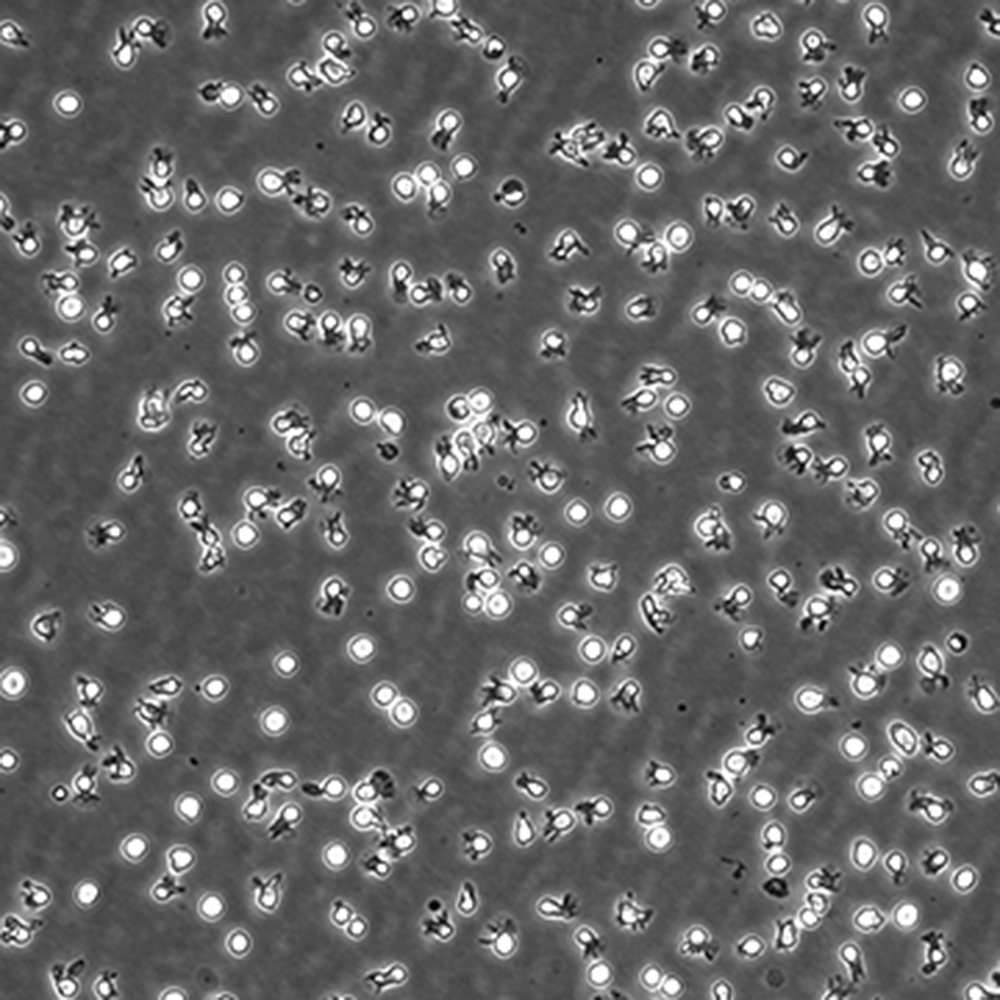

中文名稱 人彌漫大B細(xì)胞淋巴瘤細(xì)胞

組織來源 彌漫大B細(xì)胞淋巴瘤;男性

生長特性 懸浮

培養(yǎng)基 IMDM,90%;FBS,10%;雙抗。

傳代方法 Maintain cultures at a cell concentraion between between 1 X 10(5) and 1 X 10(6) viable cells/ml.

培養(yǎng)條件 Atmosphere: Air, 95%; CO2, 5%。Temperature: 37℃